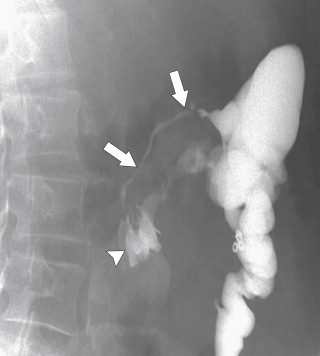

The imaging features are similar to those described in the small bowel, although the imaging of colonic Crohn disease can, at times, mimic those of UC. However, there are a number of distinguishing features that help to differentiate the two diseases ( Table 5-3 ). Plain radiography may demonstrate mucosal thickening ( Fig. 5-19 ) or toxic megacolon. Contrast enema studies (usually barium) may demonstrate involvement of the whole colon (which is therefore difficult to distinguish from UC), but this is uncommon. More commonly a variable segment of the colon is affected ( Fig. 5-20 , A ), and the disease may or may not involve the rectum. Acute disease at CT may present with mural stratification similar to that in the small bowel, representing mucosal and serosal hyperemia with submucosal inflammation or simple mural thickening and mesenteric edema ( Fig. 5-20 , B ). Aphthous ulceration is characteristic of Crohn disease ( Fig. 5-21 ). As in the small bowel, the mucosa in active disease enhances avidly after the administration of IV gadolinium. Although CT is easier and faster to perform, many patients with Crohn disease are young and may require repetitive assessment of the extent of their disease, so avoiding the radiation dose from multiple CT images is preferable. Therefore MRI is often advised, and newer MR enterographic techniques, particularly of the small bowel, have proved highly effective for evaluating the extent of disease ( Fig. 5-22 ). Furthermore, the extent of perianal disease is best imaged with MRI, which can outline the relationship of inflammatory disease to the internal and external anal sphincters; this is important to determine whether surgical repair is needed.

Figure 5-21, A, BE in a 36-year-old woman with numerous apthous ulcers ( arrows ) in the left colon from Crohn disease. B, Magnified view of apthous ulcers ( arrow ) in the distal transverse colon.

Figure 5-22, Axial fat-saturated postcontrast T1-weighted images in a 22-year-old woman with focal Crohn disease of the ascending colon ( A, arrows ). B, Coronal view demonstrates mucosal enhancement and mural thickening ( arrow ).